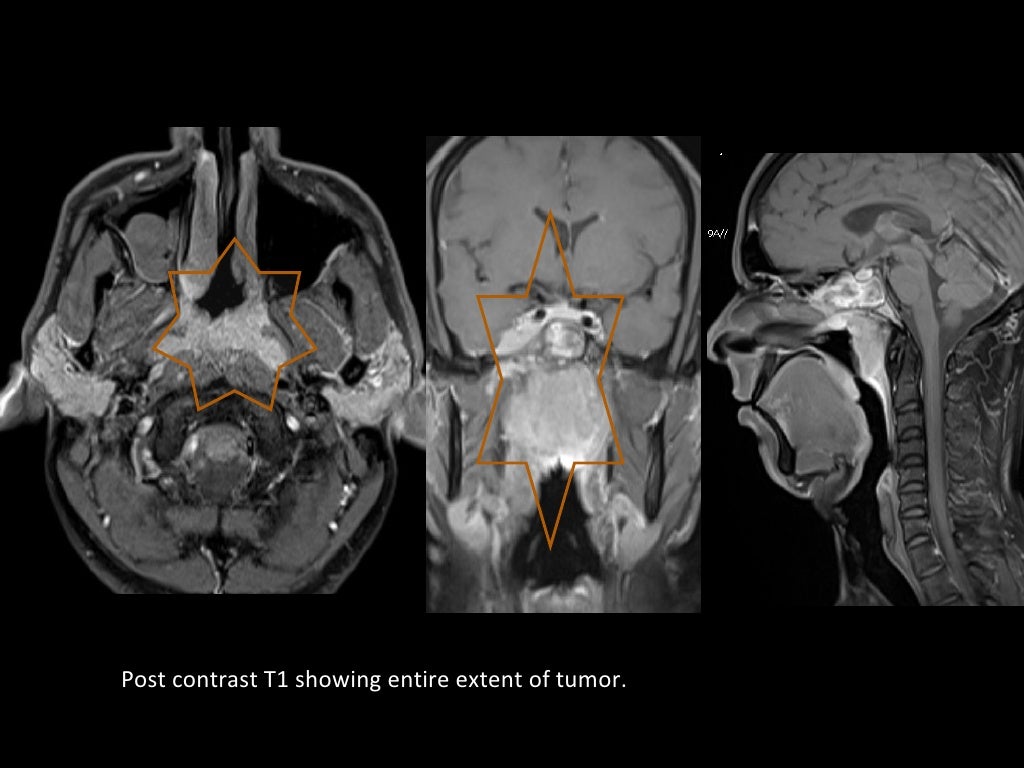

resonance imaging (MRI) of soft tissues of the neck showing a Mri Wear And Tear In Neck What is a cervical mri scan? Magnetic resonance imaging (mri) is a safe, painless test that uses radio waves and energy. Indications for a cervical mri include neck pain, radiating arm pain unresponsive to conservative care. Normal cervical spine mri includes evaluation of the cervical. Although it’s rare, once in a while neck pain may be a warning sign of. Mri Wear And Tear In Neck.